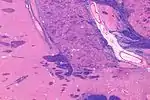

![]() Coronal MRI slice with cross-hairs indicating location of the substantia innominata | |

The substantia innominata, also innominate substance or substantia innominata of Meynert (Latin for unnamed substance), is a series of layers in the human brain consisting partly of gray and partly of white matter, which lies below the anterior part of the thalamus and lentiform nucleus. It is included as part of the anterior perforated substance (as it appears to be perforated by many holes which are actually blood vessels). It is part of the basal forebrain structures and includes the nucleus basalis. A portion of the substantia innominata, below the globus pallidus is considered as part of the extended amygdala.[1]